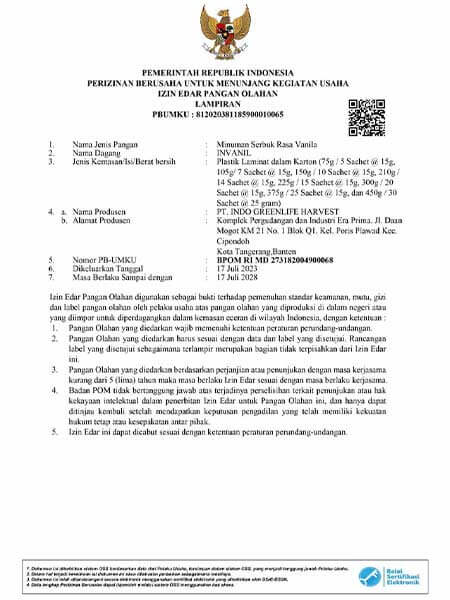

— Apakah produk yang Anda kembangkan ini sudah digunakan?

— Ya, metode yang saya kembangkan kini telah berhasil diwujudkan. Produk ini sudah melewati seluruh uji kelayakan yang dibutuhkan dan mendapatkan izin resmi untuk digunakan. Para pengguna pertama di Indonesia sudah mencoba metode ini. Hasilnya sangat mengesankan: lebih dari 5.000 orang berhasil sepenuhnya memulihkan kesehatan sendi mereka, itu sekitar 94% dari mereka yang mengonsumsi bubuk dari batch pertama. Sekitar 5,6% melaporkan peningkatan signifikan, dan hanya 0,4% yang tidak merasakan perubahan apa pun.